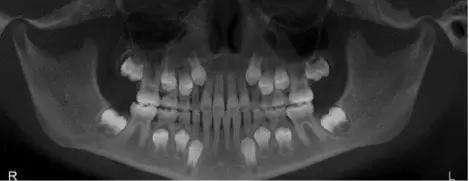

很多人都不知道自己有多少颗牙齿也不知道长多少颗牙齿是正常的 人有两副牙齿一副是乳牙一副是恒牙乳牙20颗78个月时开始萌出在2岁半基本出齐然后在6-12岁之间陆续脱落由恒牙代替 恒牙28-32颗.

人 有 多少 颗 牙齿. 31 有用 kylegun 2015-04-30. 综上所述牙齿贴面实际的价格取决于 做多少颗 在什么地区的哪类口腔机构公立私立还是莆田 什么水平的医生给做是否专业美学修复医生 做什么材质的牙齿贴面树脂还是全瓷品牌和工艺. 不知道自己有没有长智齿那就回家拿起镜子张大嘴数一数自己有多少颗牙齿便知道了 一般来说正常牙齿是28颗4颗智齿共32颗 如果你的牙齿是28颗那说明你长智齿了.